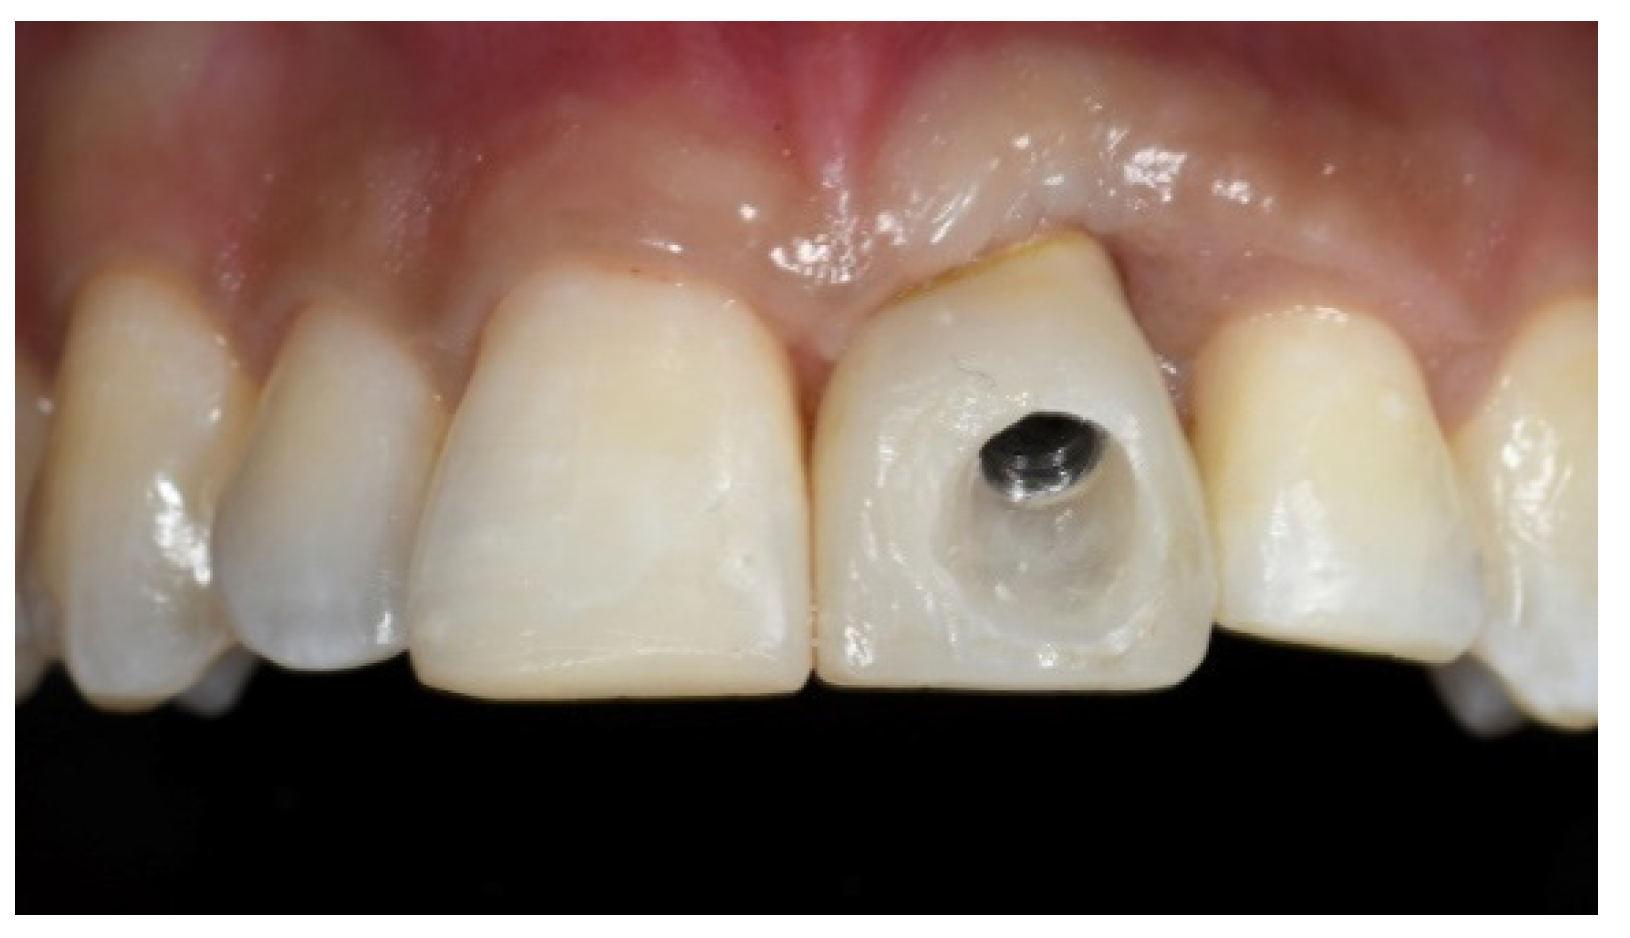

Tissue Recession around a Dental Implant in Anterior Maxilla: How to Manage Soft Tissue When Things Go Wrong?

2. Case Presentation